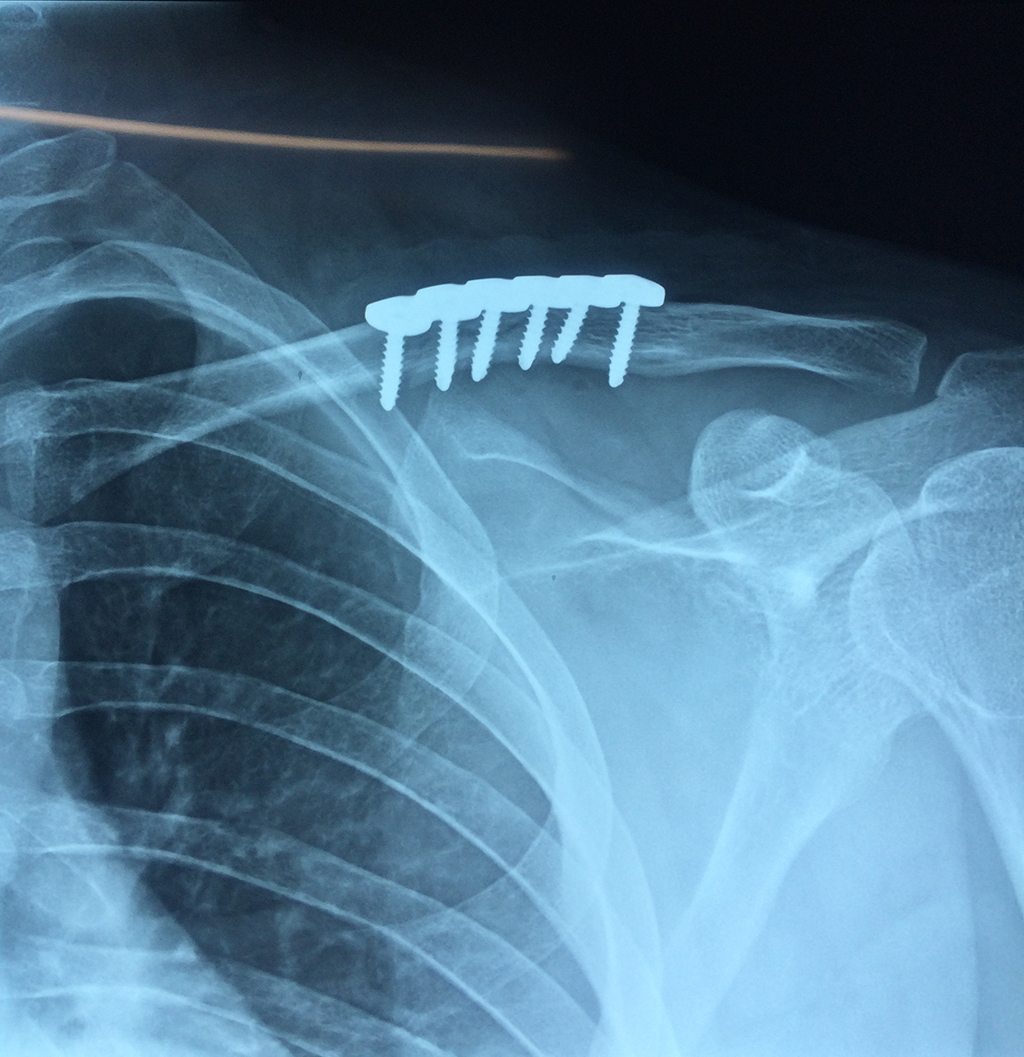

Cirugías de Codos - Clavícula

La clavícula es un hueso largo, con forma de "S" itálica, situado en la parte anterosuperior del tórax. Junto con la escápula forman la cintura escapular. Se puede palpar por toda su longitud y se extiende del esternón al acromion de la escápula, siguiendo una dirección oblicua lateral y posterior.

Se considera el único medio de unión entre el miembro superior y el tórax. A pesar de su aspecto, similar al de un hueso largo, posee una estructura semejante a la de un hueso plano, ya que carece de epífisis y de diáfisis, lo que la harían entrar dentro de la clasificación de hueso largo. Carece de un canal medular propiamente dicho.